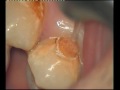

Възстановителна Дентална МедицинаОтстраняване на кариозна маса с лазерВидяно: 3933 пъти | Коментари: 0 |